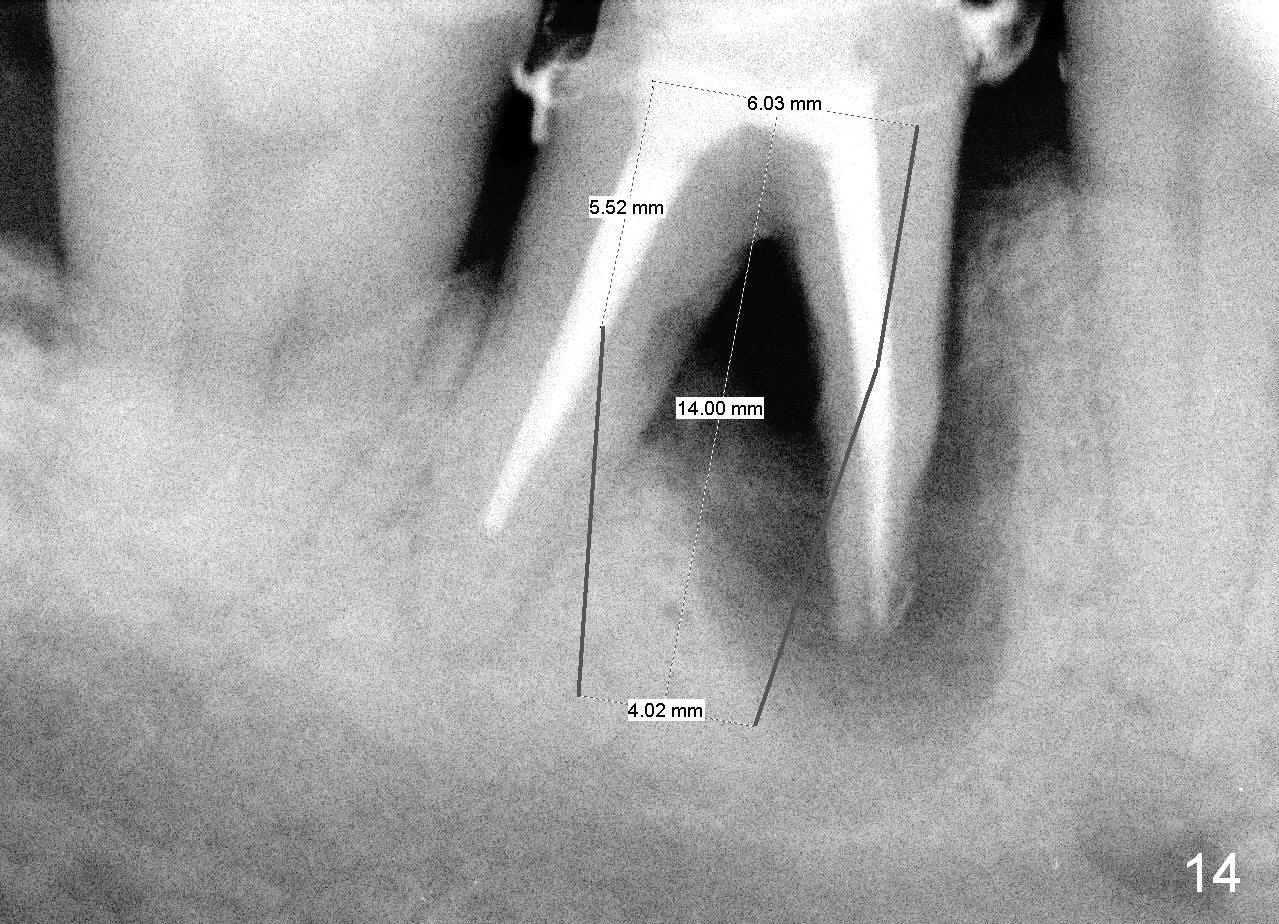

As to where to place an implant, we try to engage the largest tap (8 mm in diameter) into the mesial socket without binding. The buccal plate of the mesial socket is missing.  It is risky to extend osteotomy in the mesial socket.  Besides, the septum (Fig. 4 S) is not as tall as the distal socket (D).  It appears that the distal socket is the safest place to place an implant.  Furthermore, no drill is used for distal osteotomy.  Instead two osteotomes (3.5x15 and 4x15 mm tapered osteotomes) are used to expand the distal socket with intention to push the septum mesially.  Since the bone density is high, the osteotomes seem not to work as effectively as expected.  Then a 4.5x17 mm tap is placed at the depth ~ 14 mm with stability (Fig.5).  Finally a 5x14 mm tissue-level implant is placed with insertion torque >60 Ncm (Fig.6).  Allograft is placed in the mesial socket and buccal aspect of the distal socket, followed by insertion of collagen plug and membrane (Fig.7).  After insertion of an abutment (Fig.8 (taken 6 days postop) *), perio dressing (P) is applied to cover the wound.  There is no postop paresthesia.

When the perio dressing is removed in office 24 days postop (Fig.9), the rough surface of the implant (R) is exposed buccally.  Normally the smooth surface should contact the gingiva (S).   Lingually implant/gingiva position is within normal limit (Fig.10).  The patient returns for restoration 4 months postop (Fig.11,12).  There is bone formation in the mesial socket and new bone appears to have grown toward the implant (Fig.11 <).  A straight abutment appears to be in the middle of the edentulous space (Fig.12 A).   But it is difficult to seat the crown.  Three months post cementation, the patient complains of food impaction mesially (Fig.10 ^), although bone density continues to increase in the mesial socket and there is no mesial coronal thread exposure (*).  Retrospectively the implant should be tried to be placed in the septum as much as possible to have a favorable restorative axis (Fig.14).  The crown is re-fabricated with larger mesial contact area.  It is temporarily cemented because of slightly loose distal contact (Fig.15).  A few days later, the patient requests permanent cementation, because although the distal contact is loose, it is easy to remove food.  Mesial food impaction is less likely, but it is more difficult to be removed.